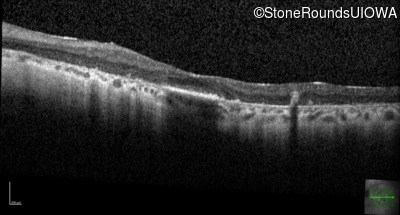

Optical Coherence Tomography - Right - 20/70

Exemplar / OCT Stack